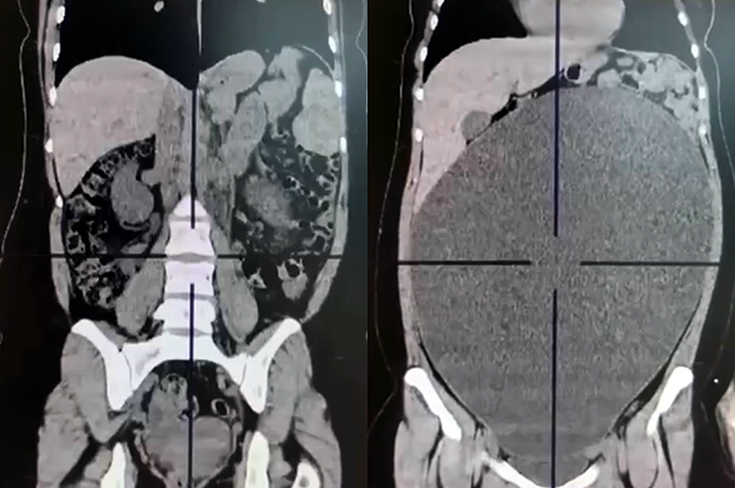

В московскую Городскую клиническую больницу №15 им. О.М. Филатова обратилась 20-летняя девушка с жалобами на боль, вздутие, увеличение объема живота и отсутствие стула. Пациентке провели компьютерную томографию с контрастированием, которая выявила образование яичника диаметром почти 40 см.